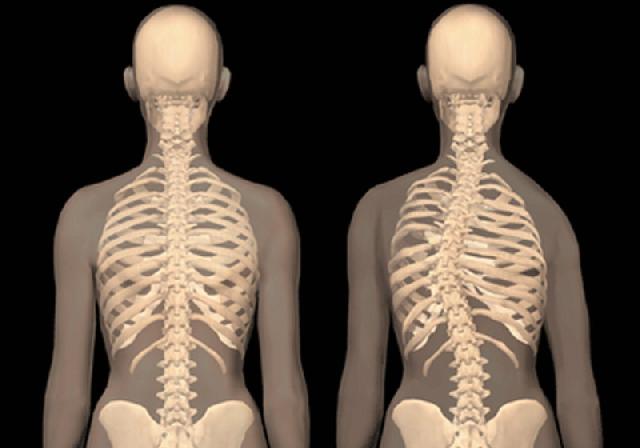

Kenali Bentuk Abnormal Pada Tulang Belakang

JAKARTA (RIAUMANDIRI.co) - Beberapa orang mungkin mempercayai bahwa skoliosis, yaitu lengkungan abnormal pada tulang belakang adalah suatu kondisi yang hanya berkembang selama masa remaja. Namun ternyata, skoliosis juga bisa muncul saat usia dewasa.

Sebenarnya ada dua jenis berbeda dari skoliosis saat dewasa menurut spesialis tulang, Dr, Manny. Ketika seorang pasien mengembangkan kondisi ini saat mereka sudah dewasa, hal ini disebut dengan “de novo”. Skoliosis de novo ini biasanya muncul setelah usia 50 tahun dan biasanya disebabkan oleh degenerasi disk dari arthritis atau degenerasi tulang belakang.

Pada bentuk lainnya dikenal sebagai skoliosis idiopathic dewasa. terjadi ketika kurva sudah ada saat masa remaja dan berkembang saat dewasa. Namun tidak seperti skoliosis degeneratif, skoliosis idiopathic tidak diketahui penyebabnya, dilansir dari foxnews,beberapa pekan lalu.

Ia menambahkan,”jika Anda membayangkan skoliosis yang berbentuk seperti huruf C, otot-otot yang berada di luar C, akan mendapatkan lebih banyak ketegangan dan stres. Mereka juga bekerja lebih keras daripada otot-otot yang berada di bagian dalam.”